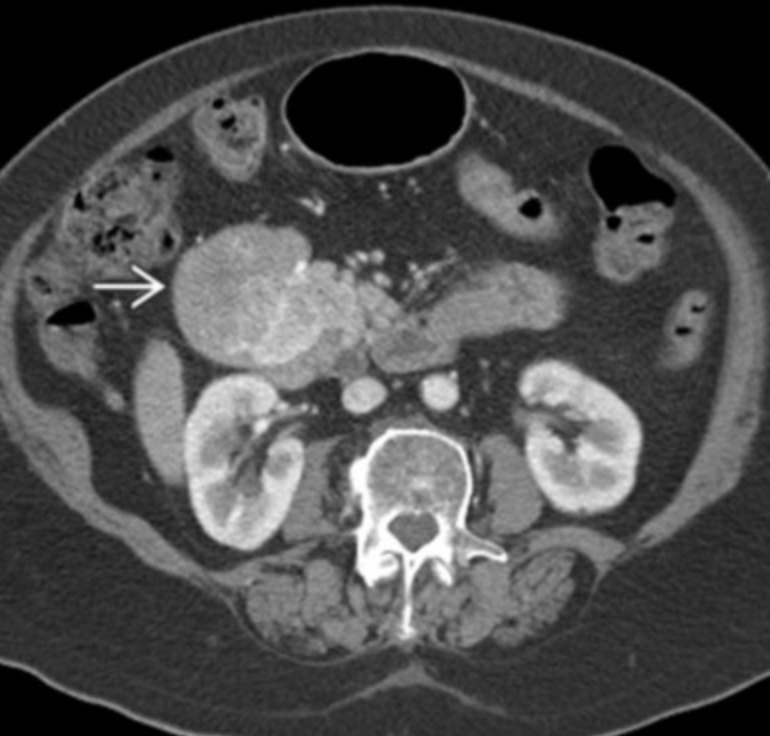

Carcinoid

• Calcified mesenteric mass

• Tethering of bowel